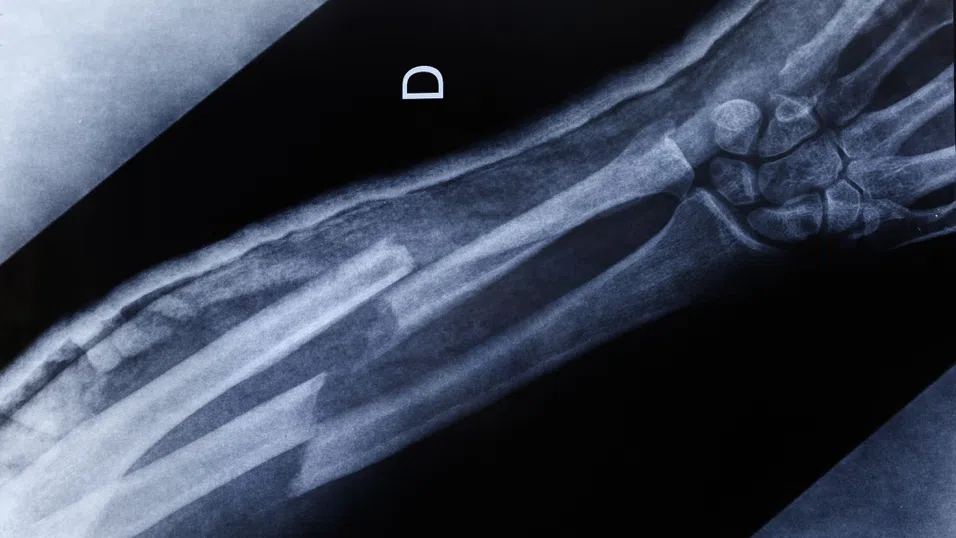

Човешките кости непрекъснато се обновяват. При остеопороза този баланс се нарушава – разрушаването на тъканта надделява над изграждането ѝ. С времето това води до отслабване на костите и повишава риска от фрактури.

Заболяването се развива с бавни темпове и често остава незабелязано до първия счупен крайник. Възраст, пол, генетика, медикаменти, хранителни навици, тютюнопушене и алкохол са сред познатите рискови фактори. Към тях сега учените добавят и един нов фактор – микропластмасите.

При животински изследвания учените установяват, че натрупването на микропластмаси води до намален брой бели кръвни клетки – индикатор за нарушена функция на костния мозък. Наблюдавани са и изменения в микроструктурата на костите, което увеличава риска от деформации и счупвания.